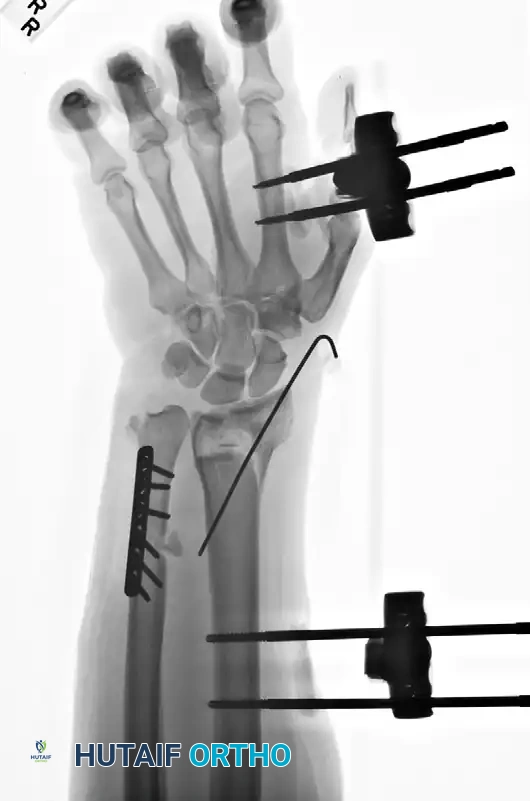

Case Example: Essex-Lopresti Reconstruction

The following sequence demonstrates the complex management of an Essex-Lopresti injury complicated by radial shortening.

Figure 57-80A: Initial presentation showing radial head fracture and longitudinal instability.

Figure 57-80B: Associated DRUJ disruption and ulnar variance.

Figure 57-80C: Attempted initial stabilization.

Figure 57-80D: Progressive proximal migration of the radius due to unrecognized or inadequately treated IOM disruption.

Figure 57-80E: Application of an external fixator; however, profound radial shortening and ulnocarpal impaction remain evident.

Figure 57-80F: Definitive revision surgery utilizing a radial head prosthesis to restore the proximal buttress and reestablish anatomical radial length.